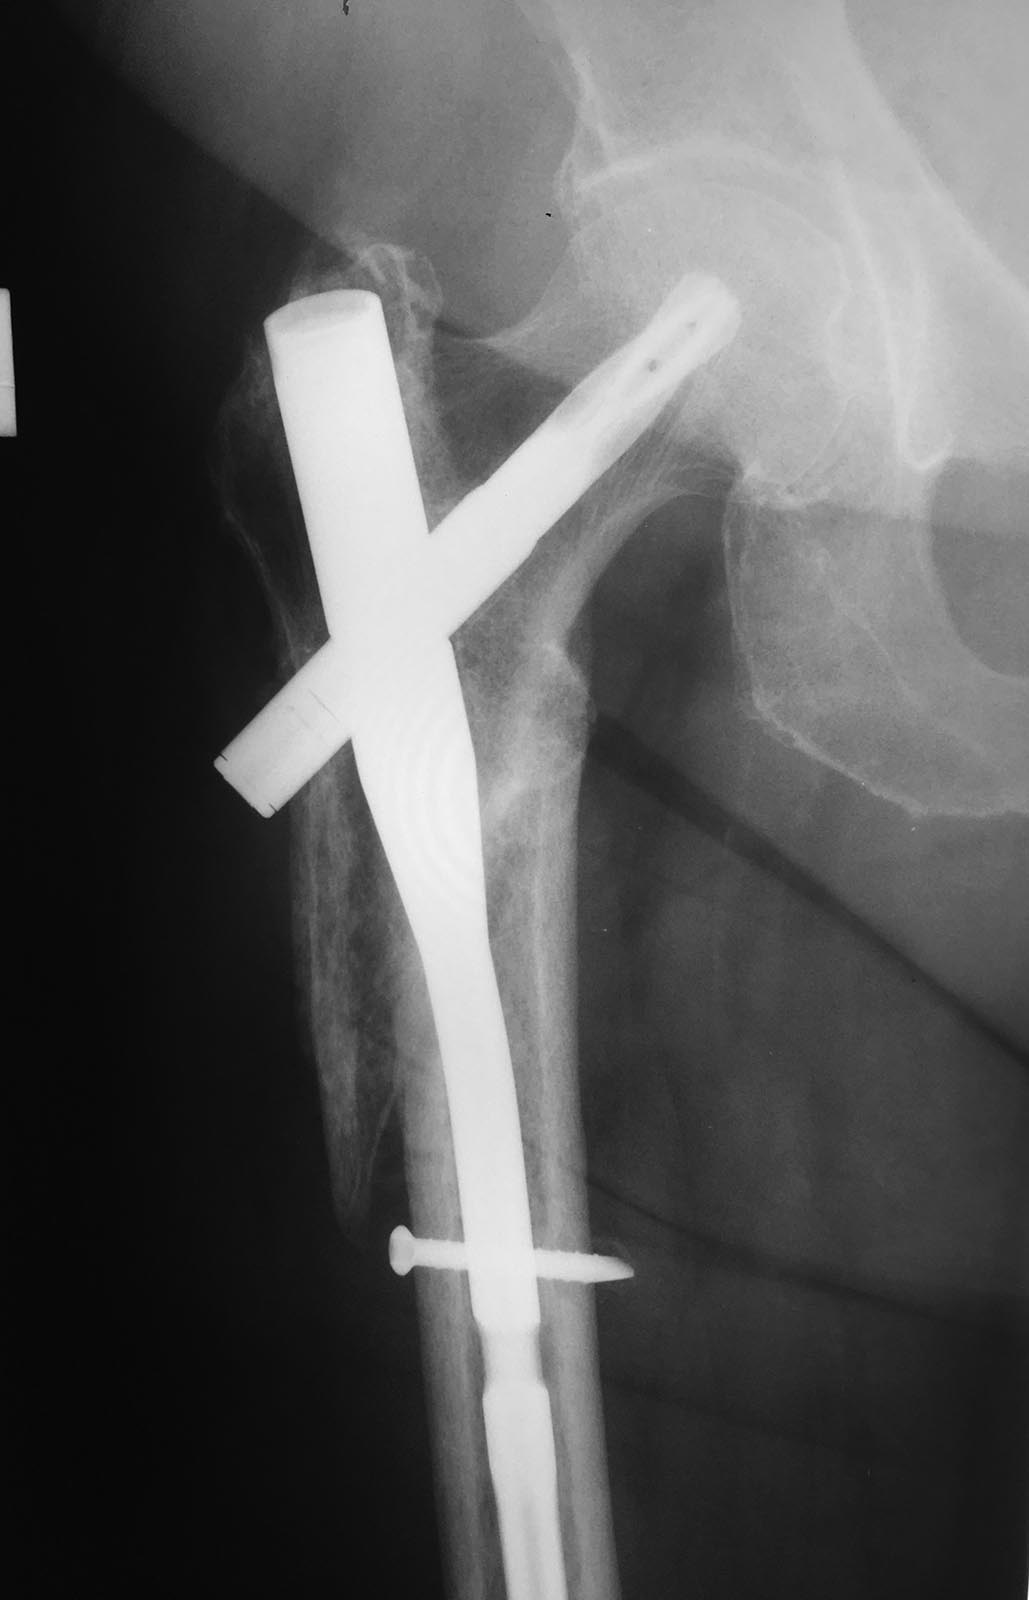

Ваше мнение о тактике ведения пациентки через 6 месяцев после остеосинтеза.

Пациентка 72 лет. 6 месяцев назад остеосинтез подвертельного перелома

бедренной кости.

Ходит с костылем. Впервые обратилась на прием 2 месяца назад.

Передвигалась с 2 мя костылями, рекомендовал перейти на 1 костыль. На

сегодняшний день опереться на ногу оторвав здоровую от пола не опираясь

руками не может. Аксиальный снимок к сожалению рентгенологи не могут